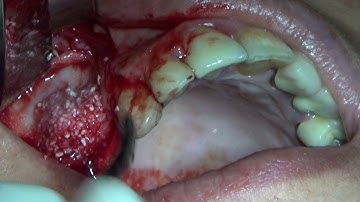

Horizontal GBR with Titanium Mesh and Tenting Screws